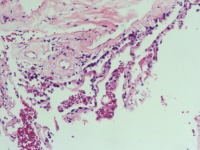

CT示左肺节段性肺不张 合并占位 既往有前列腺Ca病史

肺穿刺活检

0.5*0.3*0.2cm灰红碎组织

老师您好,这几个图片貌似没有恶性病变呀

慢性炎。